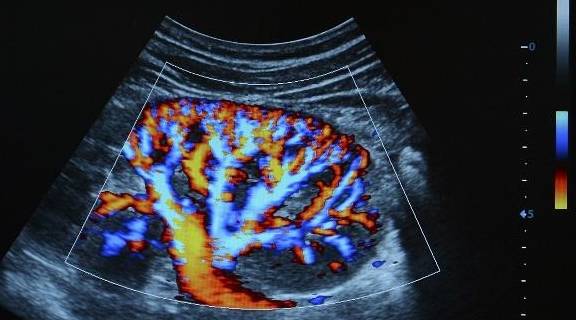

【肾脏|为何“肾脏病”越来越多?提醒:3个指标得不到控制,会伤肾】肾脏位于腰腹 , 左右各一 , 外形似扁豆状 。 每个肾脏由100多万个肾单位组成 , 而每个肾单位包括肾小球、肾小囊和肾小管 。

慢性肾脏病是持续蛋白尿和(或)肾小球滤过率低于60 , 其主要病因是糖尿病肾病、高血压肾病、肾小球肾炎等 。